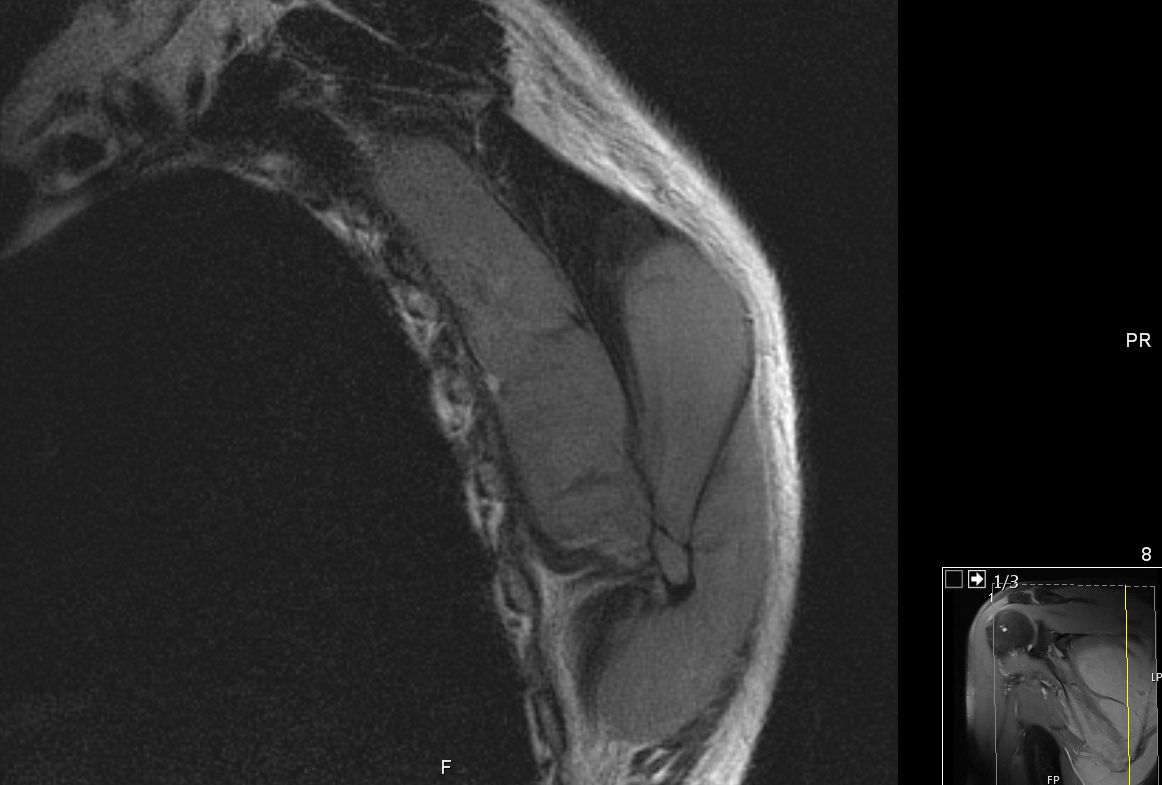

63-jähriger Mann, der vor 5 Jahren eine T - Promyelozyten - Leukämie hatte. Nach ASCT bisher rezidivfrei. Jetzt beschwerden in der rechten Schulter. Das MRT zeigt intramuskuläre Raumforderungen. Die Biopsie ergab Infiltrate der APL.